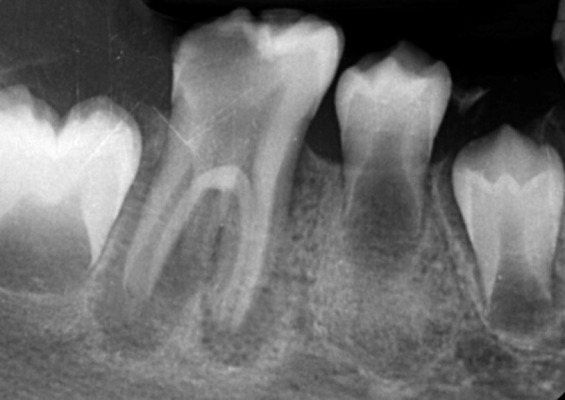

Regenerative endodontic procedures (REPs) have emerged as a biologically driven approach for managing immature teeth with necrotic pulp and open apices, providing an alternative to traditional apexification techniques. This case report describes the successful treatment of a three-rooted immature mandibular first molar with necrotic pulp and chronic apical periodontitis in a 9-year-old patient using REPs. The treatment followed the guidelines set by the American Association of Endodontists and utilized a two-visit protocol. Concentrated growth factor (CGF) was employed as a biological scaffold in the root canals, while calcium-enriched mixture (CEM) cement was used for the coronal seal. Radiographic evaluations conducted at 6, 12, and 15 months revealed progressive periapical healing, significant root elongation, increased thickness of the root walls, and partial apical closure. Clinically, the patient remained asymptomatic during all follow-ups. This case highlights the potential of CGF and CEM cement-enhanced REPs to promote continued root development and achieve predictable outcomes in immature teeth with necrotic pulps, offering a biologically based alternative to conventional apexification.